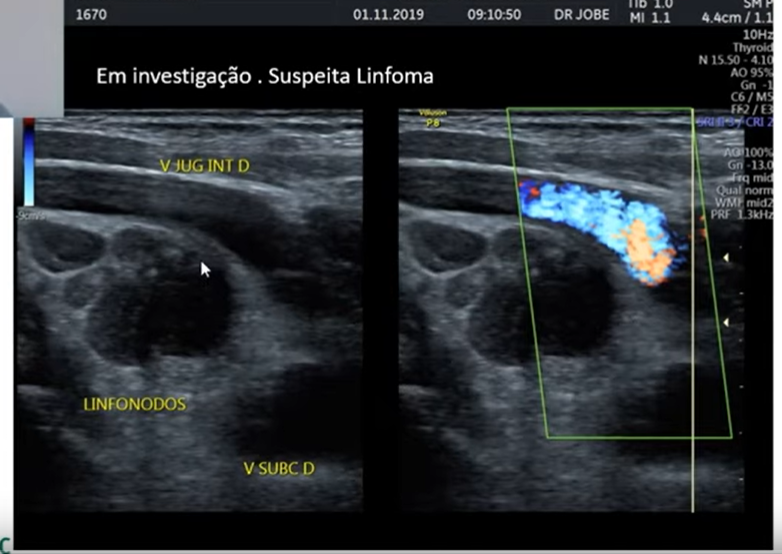

Podemos verificar linfadenomegalia no USG? É um diganóstico diferencial para massa cervical?

Sim!

Quando devemos suspeitar de malignidade em linfonodomegalia?

Quando o diametro perpendicular a pele for mais que o paralelo.

Quando a vertical for maior que a horizontal.